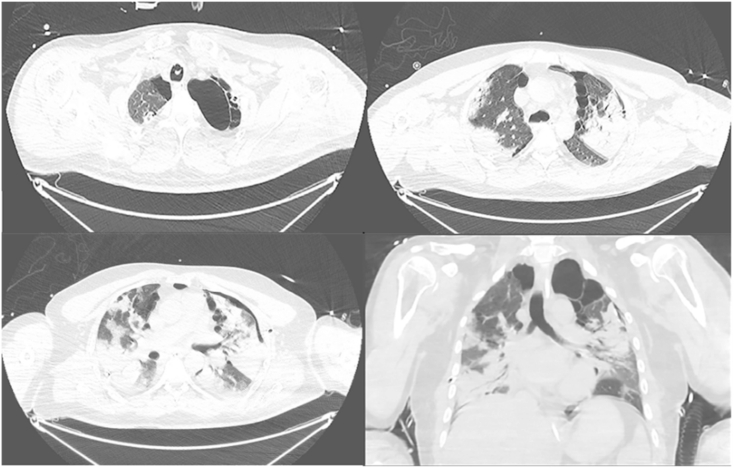

A CT chest scan (Fig. 4a–d) showed resolution of the right sided pneumothorax, but ongoing left mild anterior pneumothorax. There were bilateral apical air cysts, mainly subpleural, more so in the left lung, and paraseptal emphysema. There was extensive bibasal consolidation.

Fig. 4.

Bilateral predominantly apical lung air cysts mainly subpleural and more left sided. Bilateral extensive pneumonic consolidative patches more confluent in the bases. Residual left anterior pneumothorax.

The CT scan of our patient carried out after 2 weeks of illness also showed presence of bilateral air cysts and paraseptal emphysema. It is likely that rupture of these cysts was secondary to mechanical ventilation and resulted in a subsequent right sided pneumothorax.